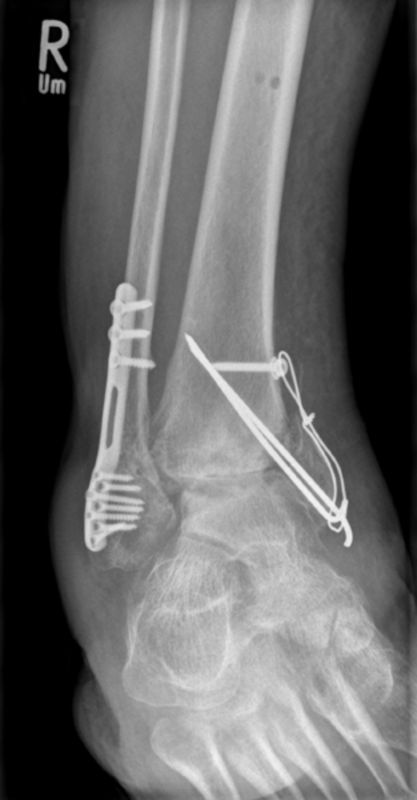

Vorgeschichte: Herr M. zog sich vor drei Jahren im Rahmen eines BG-lich versicherten Motorradunfalls eine I°ig offene mehrfragmentäre Tibiaquerfraktur mit 2-Etagen-Fraktur der Fibula links sowie eine OSG-Luxationsfraktur rechts zu.

Die initiale Versorgung erfolgte in einer Klinik der Maximalversorgung mit Fixateur extern Anlage und Transfixation des Sprunggelenks. Im Verlauf erfolgte der Verfahrenswechsel auf einen Tibia-Nagel links und Fibulaplatte mit Zuggurtung des Innenknöchels rechts.

Vorstellung in einem Zentrum: Ein Jahr nach dem Unfall erfolgte bei persistierenden Schmerzen die erstmalige Vorstellung in einer BG-Klinik. Hier zeigte sich eine Subluxationsstellung der Sprunggelenksfraktur auf der rechten Seite mit weit fortgeschrittener posttraumatischer Arthrose. Auf der linken Seite zeigte sich eine befriedigende Stellung bei noch erheblicher Defektzone lateralseits und nicht ganz aufeinander stehenden Frakturenden aber in regelrechter Position. Es erfolgte zunächst die Sprunggelenksarthrodese rechts um eine stabile, schmerzfreie Seite zu erhalten.